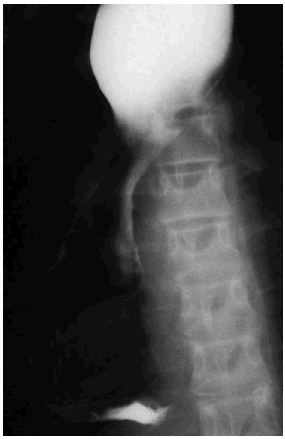

En la radiografía de tórax practicada se observó una masa en el mediastino posteroinferior (fig 1), y destacba la ausencia de burbuja aérea gástrica.

Fig. 1.